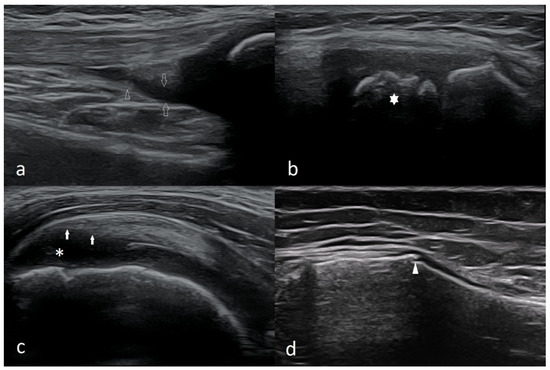

Basic Differences and Most Common Findings in Ultrasound Examinations of Musculoskeletal System in Children: A Narrative Literature Review

by Tomasz Poboży, Wojciech Konarski, Karolina Piotrowska-Lis, Julia Domańska, Kamil Poboży and Maciej Kielar

We present basic differences in the musculoskeletal ultrasound examinations between adults and children. Examiners who deal with adults on a daily basis have shared concerns about examining children. Such concerns may arise from the different approach to child ultrasounds, but they also come [...] Read more.

We present basic differences in the musculoskeletal ultrasound examinations between adults and children. Examiners who deal with adults on a daily basis have shared concerns about examining children. Such concerns may arise from the different approach to child ultrasounds, but they also come from differences in anatomical characteristics according to developmental age. We discuss the presence of growth plates, as well as non-mineralized parts of the bones. We also refer to the pathologies most often found in ultrasounds in early developmental stages. In the PubMed database, the set of keywords: “msk ultrasound in children”, “pediatric msk sonoanatomy”, “coxitis fugax”, “pediatric Baker’s cyst”, “Baker’s cyst ultrasonography”, “bone septic necrosis in ultrasonography”, “ultrasonography in juvenile idiopathic arthritis”, and “ultrasonography in juvenile spondyloarthropathies”, was used to identify a total of 1657 results, from which 54 was selected to be included in the article. We discuss the problem of osteochondritis dissecans, Osgood-Schlatter disease, examples of ligament injuries (especially in relation to the knee and ankle joints), exfoliation of growth cartilages, osteochondroma, exudates and inflammations affecting joints, and Baker’s cysts. In this way, we have collected useful information about the most common diseases of the musculoskeletal system in children. Full article

Show Figures

Figure 1